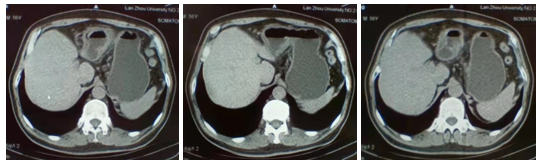

增强CT检查(2021.6.9):胃腔充盈良好,胃壁未见局限性增厚,胃窦部胃壁未见异常强化(见图5)。

图5 增强CT